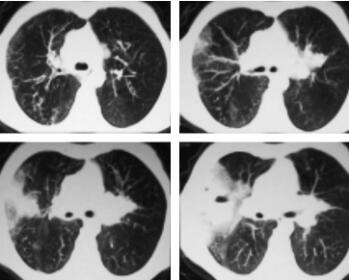

总结:右肺中叶占位性病变,阻塞性肺炎。更换抗生素为美罗培南1.0g q8h静滴,但患者仍出现发热,电子支气管镜:喉部、气管、隆突、左支气管、右支气管未见异常。支气管刷片、冲洗液、右肺支气管黏膜、痰液病理检查均未见肿瘤细胞,提示炎症细胞浸润,也未查见抗酸杆菌。右肺穿刺病理活检:送检组织为间质及肺泡腔内纤维组织增生,慢性炎症细胞浸润。肿瘤标记物、浅表淋巴结超声、骨ECT、痰培养及血培养未见明显异常。2天后复查胸部CT(图3):右肺中叶病变,其内见液化坏死,可见液平,周围斑片影较前明显扩大,增强扫描无强化,肺脓肿。

经联合抗感染治疗4天后,患者体温恢复正常。入院后第14天再次复查CT提示病灶明显缩小后出院,转回当地社区医院继续治疗。